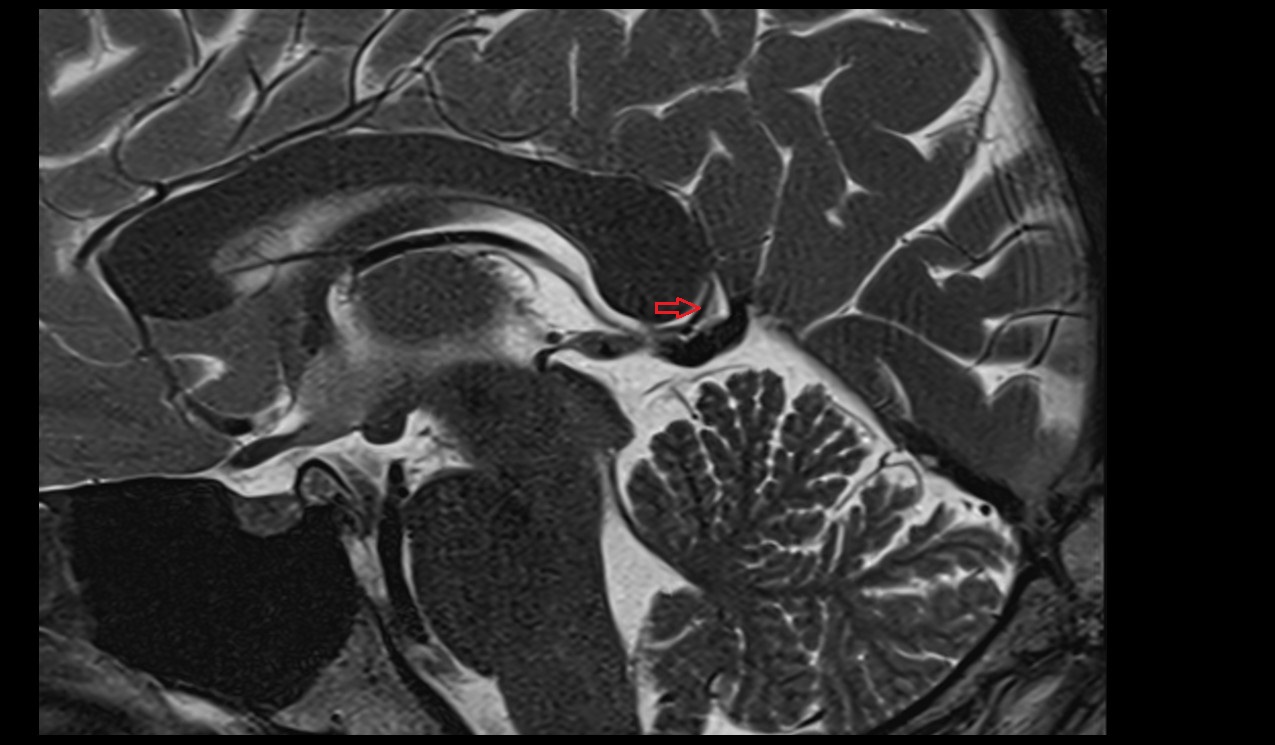

- Aqueduct of midbrain (Sylvian Aqueduct)

- Cerebral aqueduct